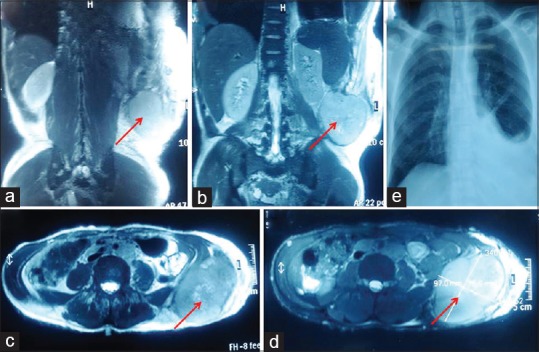

Magnetic resonance imaging (MRI) showed a well-defined round to oval large mass measures 9.7 cm × 7.5 cm in deep subcutaneous and intermuscular compartment of the left posterolateral abdominal wall. The tumor was heterogeneously hyperintense on T1 weighted and T2 weighted as compared to muscles [Figures [Figures11 and and2a2a–d].

| Figure 2:Magnetic resonance imaging T1-weighted coronal (a), T2-weighted coronal (b), T2-weighted axial (c), and STIR axial (d) images showing a well-defined round to oval large mass (arrow) in deep subcutaneous and intermuscular compartment of left posterolateral abdominal wall. The lesion measures 9.7 cm × 7.5 cm in transverse and anteroposterior dimension, respectively. The lesion is heterogeneously hyperintense on T1 weighted and T2 weighted as compared to muscles. There is no signal drop on fat suppressed sequence suggestive of absent fatty component. The central part of lesion shows T2 hyperintense areas suggestive of necrosis. There is no extension into spinal canal. Chest X-ray posteroanterior view, (e) left-sided pleural effusion

Chest X-ray showed left-sided pleural effusion [Figure 2e], and fluid cytology was reported outside as malignant, likely sarcoma. An excision biopsy was done from one of the inguinal lymph nodes. The histological section showed complete effacement of the nodal architecture and infiltration by a tumor arranged in sheets with few remnants lymphoid follicles [Figure 4a]. The cells showed eccentrically placed large nucleus with vesicular chromatin, prominent nucleoli, and abundant amount of eosinophilic cytoplasm. Frequent binucleation/multinucleation, nuclear lobulations, mitotic figures, and perinodal spread were noted [Figure 4b–d]. The tumor cells revealed diffuse immunopositivity for S-100 [Figure 4e] and vimentin [Figure 4f] (Both Thermo-Scientific, RTU), however negative for cytokeratin, epithelial membrane antigen, CD20, CD30, CD68, desmin, CD34, smooth muscle actin (All Thermo-Scientific, RTU), HMB-45, Melan-A, and CD3 (All Dako, RTU). INI-1 (Cell Marque; dilution 1:100) immunohistochemistry (IHC) did not show loss of expression in the tumor cells. Based on characteristic cytology, histomorphology, and IHC in a background of NF-1, a final diagnosis of epithelioid variant of MPNST with preserved INI-1 status was made. Unfortunately, the patient did not receive any chemotherapy or radiation therapy and succumbed after 1 month.